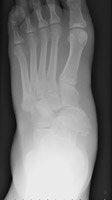

- Click on the image for a larger versionAAP radiograph of the ankle. This demonstrates the typical appearance of talonavicular dislocation.

- Click on the image for a larger versionCAP radiograph of the foot. A different patient shows talonavicular dislocation.